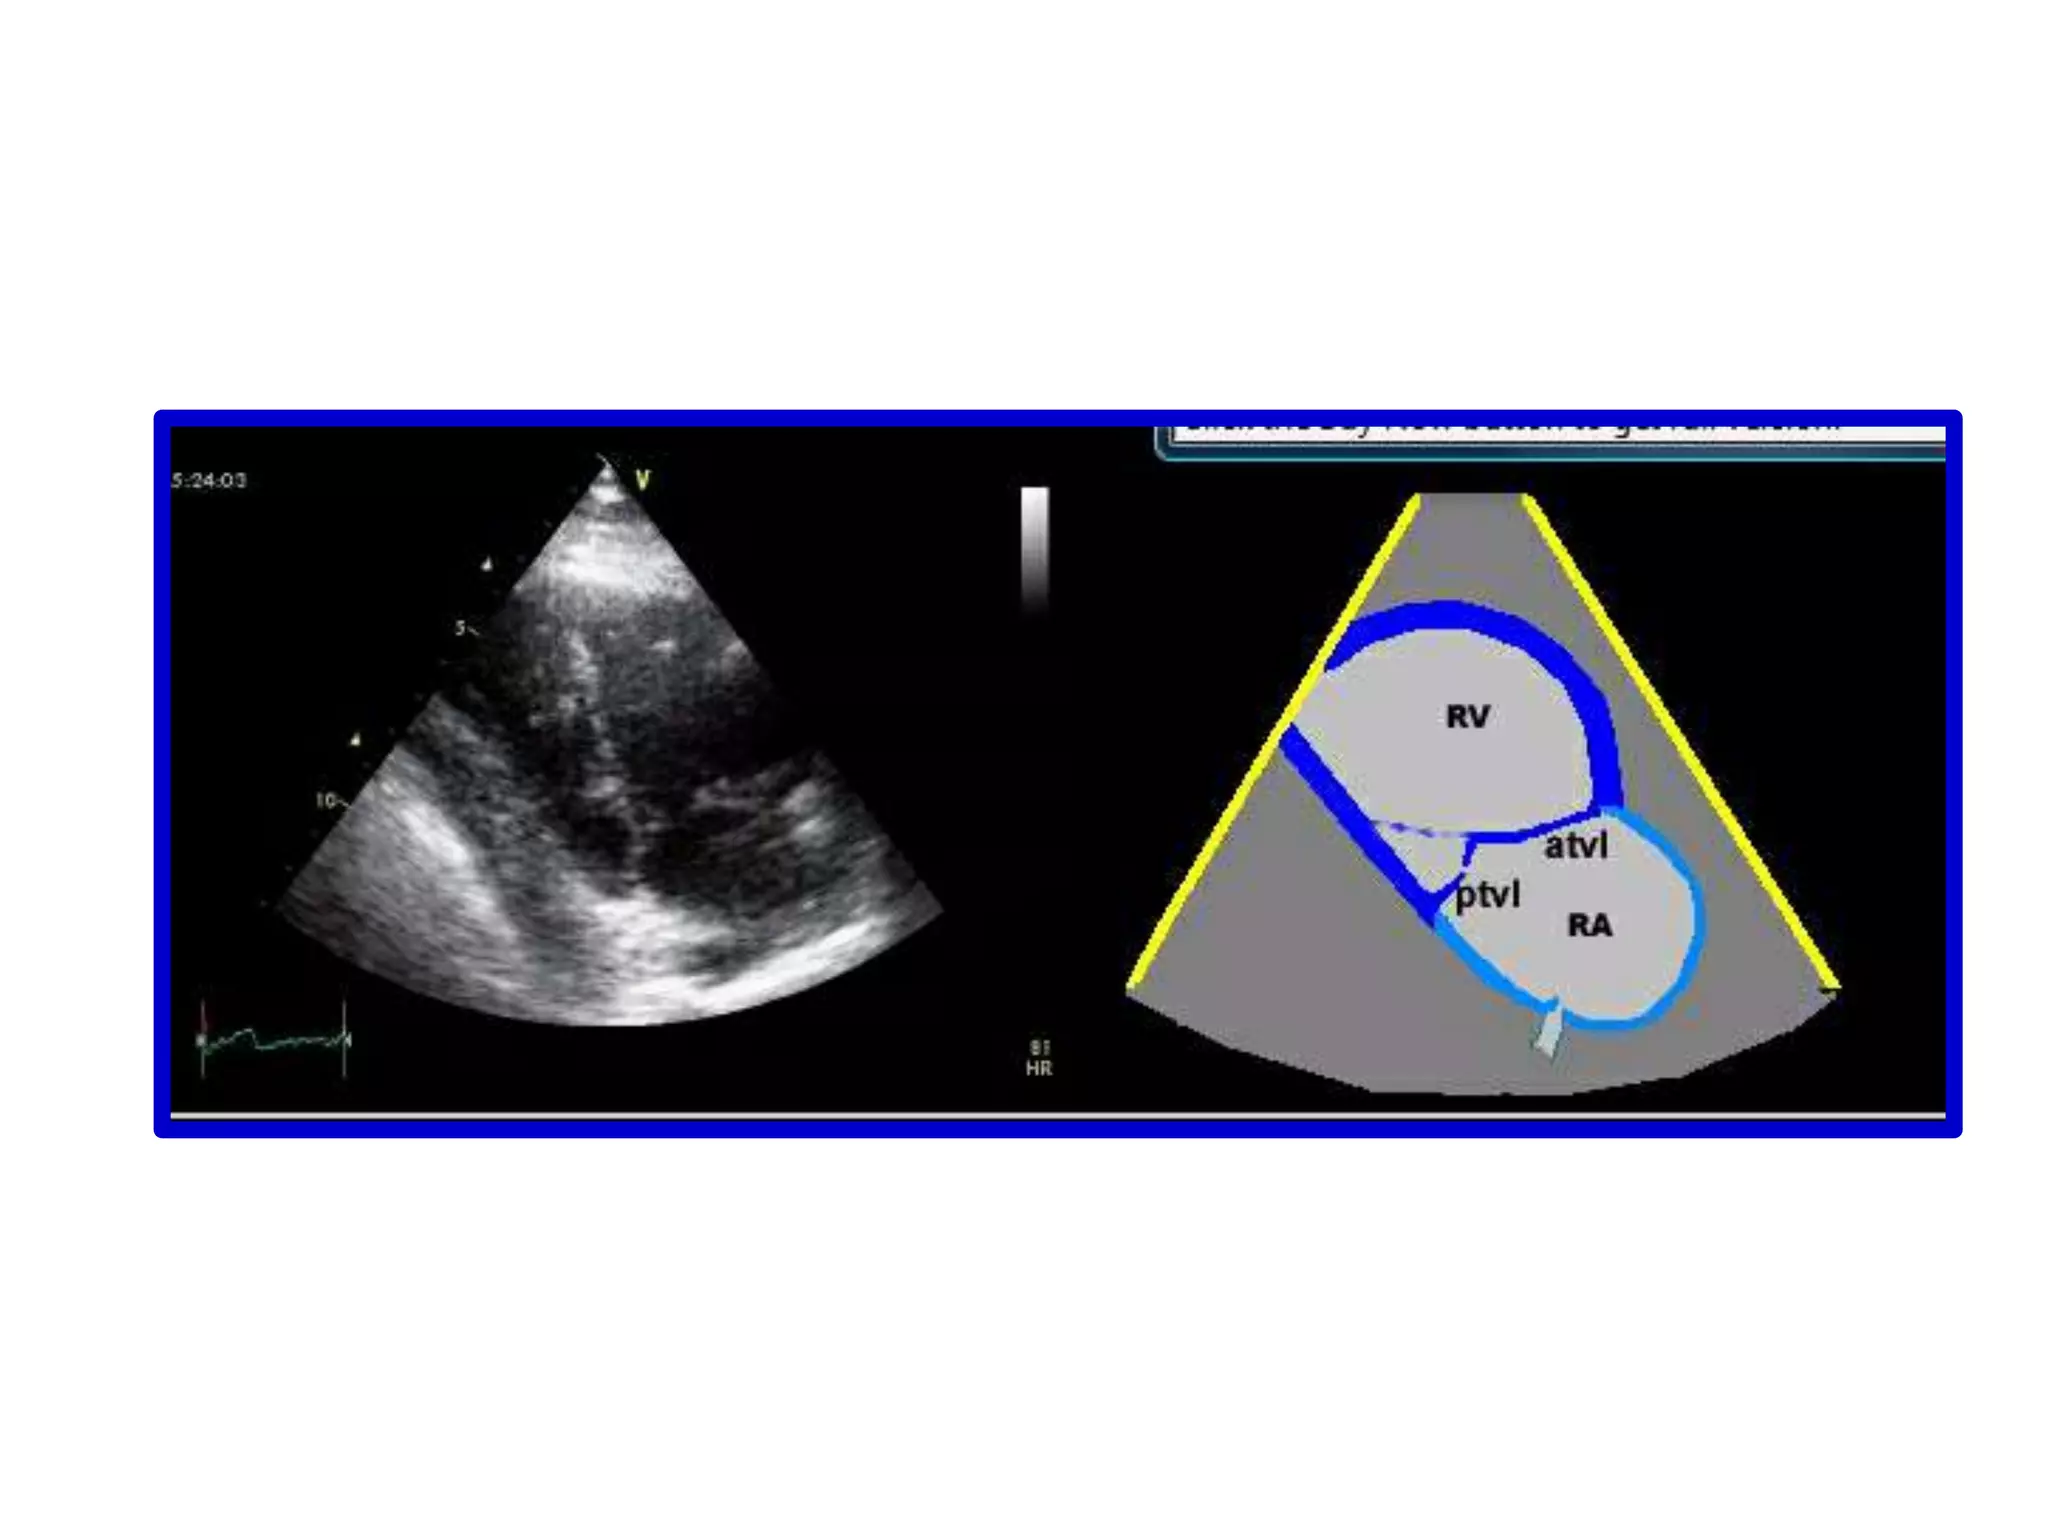

Parasternal WindowRight Long-Axis ViewSweeping begins at the right atrium which is on the right of the screen. In this view we can see the right atrium and the right ventricle, with the tricuspid valve in between

Parasternal WindowRight Long-AxisViewSweeping begins at the right atrium which is on the right of the screen. In this view we can see the right atrium and the right ventricle, with the tricuspid valve in between